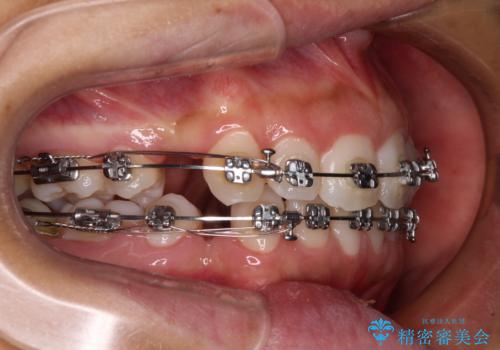

- 矯正装置

- メタルブラケット

- 出っ歯で唇が閉じにくいとのことで来院された患者様です。

顎先に力を入れないと唇が閉じきれない口元であったので、上下左右の第一小臼歯4本を抜歯して、ワイヤー装置にて矯正治療を行うこととしました。

費用を抑えるため、金属の装置を選択されました。